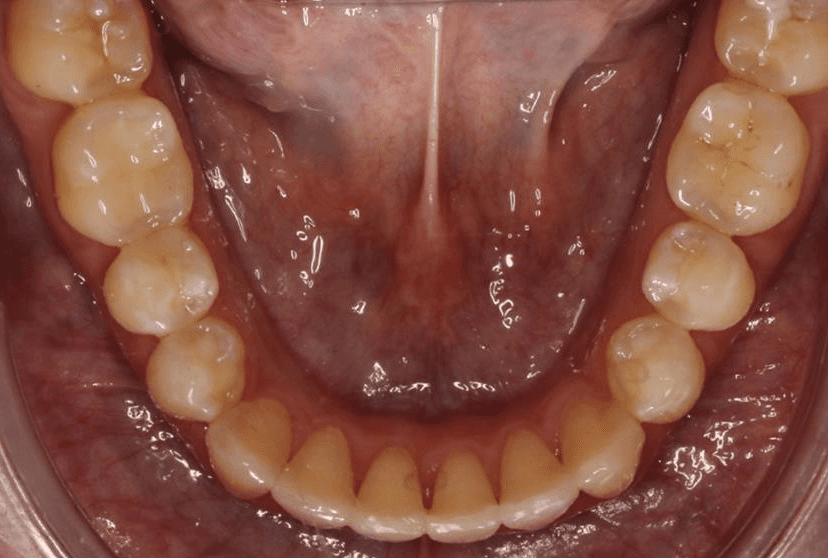

Final results

INTRAORAL

Diganosis: Moderate crowding in both arches, constricted arch forms with anterior and posterior single tooth crossbites, poor smile display